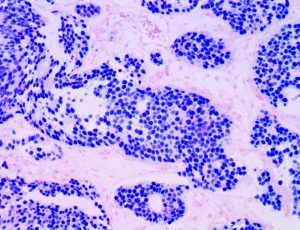

It is the ICU physician who is most likely to witness one of the deadliest manifestations of the abnormal immunological response, the cytokine storm syndrome (CSS). This response is also referred to by some as the cytokine release syndrome (CRS). CSS is characterized by continuous activation and expansion of macrophage and lymphocyte populations, which secrete large amounts of cytokines, causing the cytokine storm. This massive cytokine release is akin to hemophagocytic lymphohistiocytosis (HLH) disease, a syndrome characterized by initial unchecked and persistent activation of cytotoxic T lymphocytes and NK cells.

Clinical and laboratory manifestations of HLH include fever, enlarged liver and/or spleen, neurologic dysfunction, coagulopathy, liver dysfunction, cytopenias (i.e., low levels of erythrocytes, leukocytes, and/or platelets), hypertriglyceridemia, hyperferritinemia, hemophagocytosis, and eventually diminished NK cell activity as the immune system becomes progressively paralyzed. HLH can be familial (primary HLH) or secondary to another disease process (sHLH), such as rheumatic disease, in which it is referred to as macrophage activation syndrome (MAS, characterized by elevated ferritin).